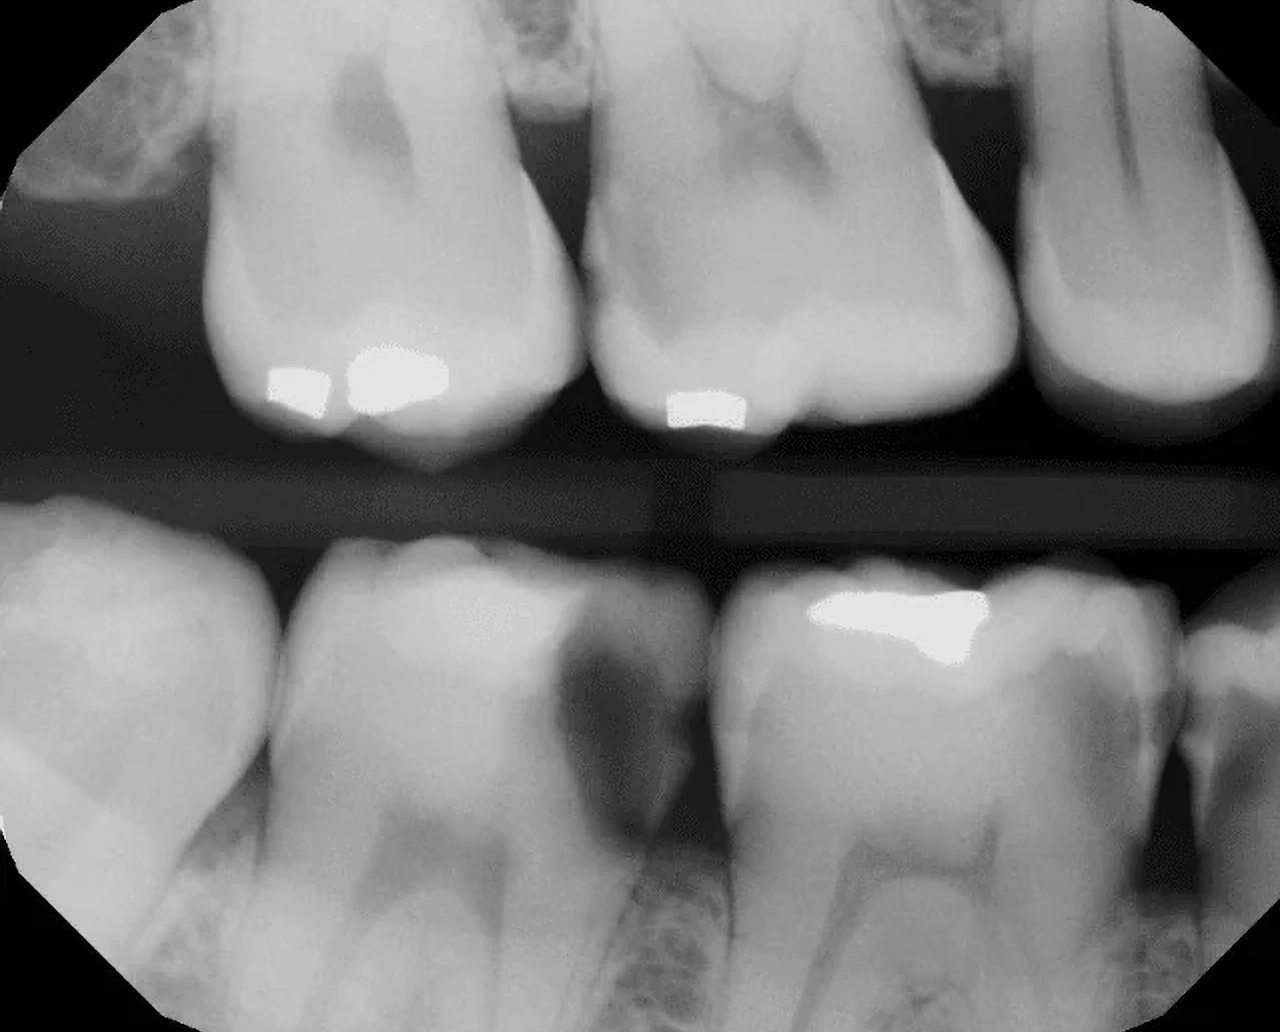

SMILE Dx® empowers dentists to diagnose cavities, PAPs and peridontal disease on the pixel level.

Patients who see their x-rays in AI are significantly more likely to accept treatment1.

“RED…

that can’t be good”

Dentist will have the technology to detect cavities, gum disease, and root canals on the pixel level. The days of “watching” a cavity get larger are over.